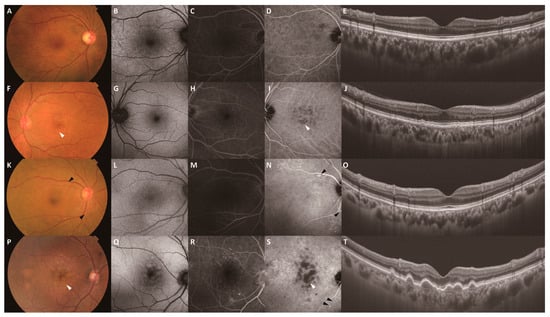

Clinical Characteristics of Punctate Hyperfluorescence Spots in the Fellow Eye of Patients with Unilateral Macular Neovascularization with No Drusen

by Hiroyuki Kamao, Katsutoshi Goto, Yuto Date, Ryutaro Hiraki, Kenichi Mizukawa and Atsushi Miki

J. Clin. Med. 2024, 13(18), 5394; https://doi.org/10.3390/jcm13185394 - 12 Sep 2024

Cited by 4 | Viewed by 1630

Objectives: To assess the clinical characteristics of patients with macular neovascularization (MNV) with no drusen in the fellow eye, we investigated the incidence of MNV in fellow eyes and the outcomes of intravitreal aflibercept (IVA) monotherapy in MNV eyes of patients with [...] Read more.

Objectives: To assess the clinical characteristics of patients with macular neovascularization (MNV) with no drusen in the fellow eye, we investigated the incidence of MNV in fellow eyes and the outcomes of intravitreal aflibercept (IVA) monotherapy in MNV eyes of patients with unilateral MNV with a punctate hyperfluorescence spot (PHS) in the fellow eye. Methods: We retrospectively studied 58 treatment-naïve patients with unilateral MNV with no drusen in the fellow eye. Patients were classified into a PHS group (n = 29) or no-PHS group (n = 29) based on the presence of PHS. We evaluated the incidence of MNV in the fellow eye, and the retreatment rate after initiation of three monthly aflibercept injections over one year. Results: Fellow eyes in the PHS group had a thicker choroid (p < 0.05) and higher prevalence of pachychoroid pigment epitheliopathy (PPE) (p < 0.001). MNV eyes in the PHS group had a thicker choroid (p = 0.09). The PHS group had a lower retreatment rate (p < 0.05) and required fewer injections (p < 0.05) than the no-PHS group. MNV developed in one eye in both the PHS and no-PHS groups, and both cases occurred in areas of hypofluorescence on indocyanine green angiography within the PPE area before the onset of MNV. Conclusions: The PHS group frequently exhibited pachychoroid disease characteristics and responded better to IVA monotherapy than the no-PHS group. These groups may represent distinct populations of patients with unilateral MNV with no drusen in the fellow eye. Full article